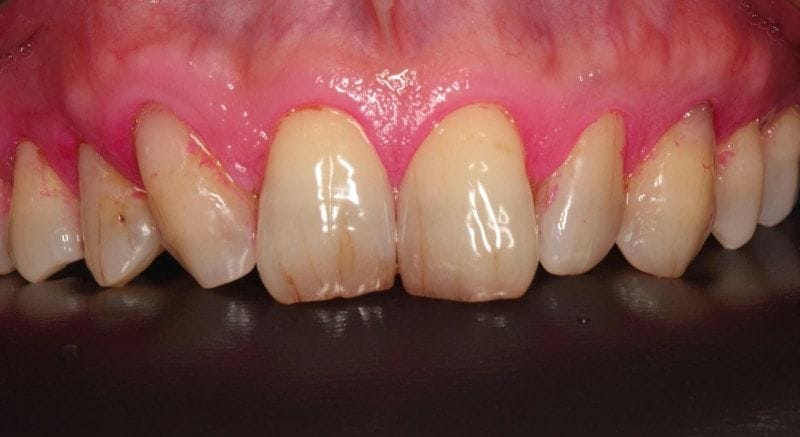

治療前

圖示:治療前Mr.Hsieh的右下側門牙、右下犬齒及口內掃描X光片